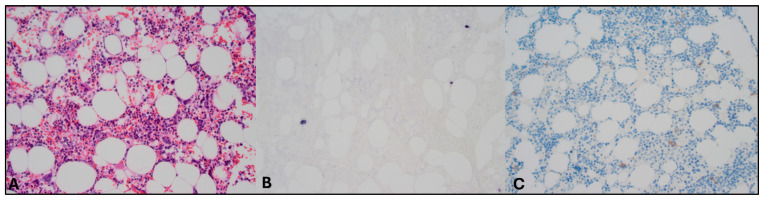

Background and Significances: In patients with Epstein-Barr virus-driven hemophagocytic lymphohistiocytosis (EBV-HLH), identifying the underlying cause poses a significant diagnostic challenge. HLH may precede overt disease, and early directed treatment for HLH can obscure histopathological findings. A liquid biopsy enables the detection of tumor-derived DNA from various sources, including cell-free DNA, circulating tumor cells, extracellular vesicles, and tumor-educated platelets, and might aid in this setting. Case Presentation: This case presents a young patient with EBV-HLH, in which genomic analysis of tumor-derived DNA from circulating tumor cells led to the diagnosis of an EBV-positive NK/T-cell lymphoma-where conventional tissue biopsies had failed. Conclusions: This report underscores the potential of the liquid biopsy as a valuable diagnostic tool in complex cases of EBV-HLH.